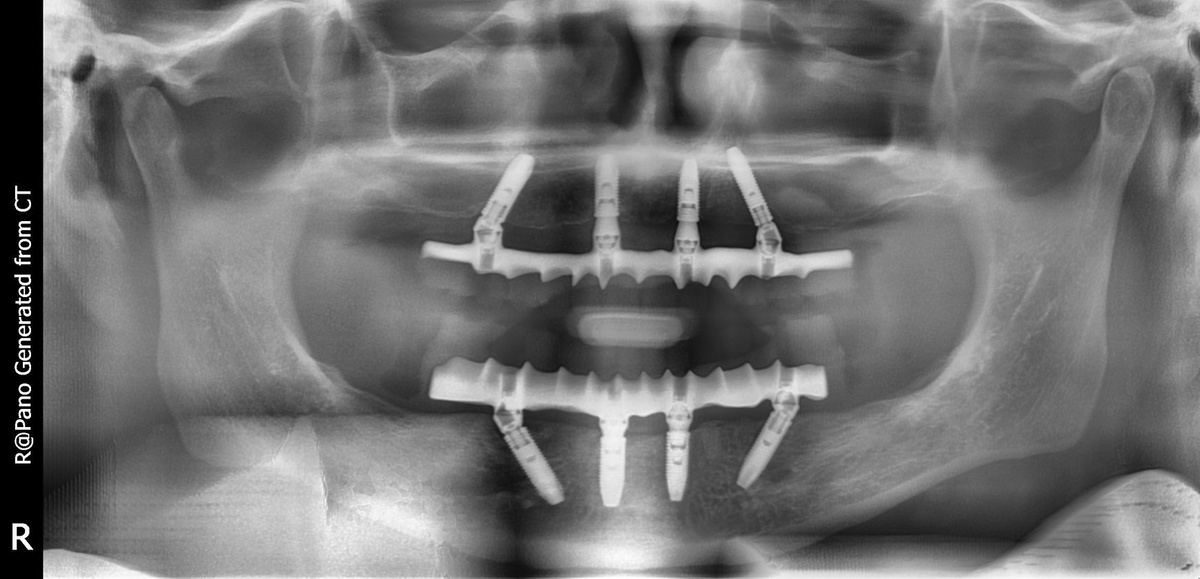

Суть методики заключается в том, что зубной ряд на полностью беззубой челюсти восстанавливается с помощью цельного несъемного протеза. Опорой для конструкции служат 4 зубных импланта, которые устанавливаются в определенную область челюсти и под определенными углами.

На снимке видно, что зубные импланты стоят под углом для обеспечения лучшей стабилизации даже при сильной атрофии кости

Огромный плюс методики в том, что она работает даже в тех случаях, когда пациент много лет носил съемные протезы и за это время челюстная кость без должной нагрузки сильно атрофировалась. Стабильности удается добиться благодаря тому, что опорные зубные импланты ставятся в челюсть под определенным углом.